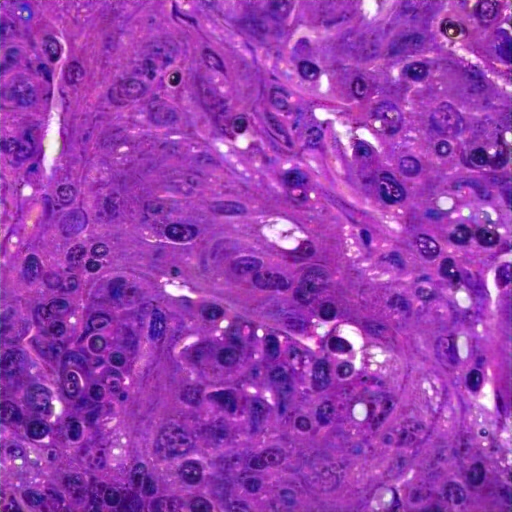

The tissue displays pleomorphism, hyperchromatic enlarged nuclei, and a high nuclear-to-cytoplasmic ratio with prominent nucleoli, indicating potential malignancy. Areas show dense cellularity, loss of normal stratification, with invasive, atypical cells and stromal invasive squamous cell carcinoma. Moderate inflammatory cells are also present. Keratin pearls confirms a poorly differentiated squamous intraepithelial lesion ( (HSIL), likely an invasive carcinoma. Active mitotic figures confirm rapid cell division a high proliferative index known as a neoplastic condition in the epithelium, along with tissue disorganization features deviates from squamous epithelium, consistent with invasive squamous cell carcinoma. Key findings include include architectural disorder and abnormal mitotic figures, and invasive, atypical cells into fibrous, inflamed stroma, with spindle-shaped cells.